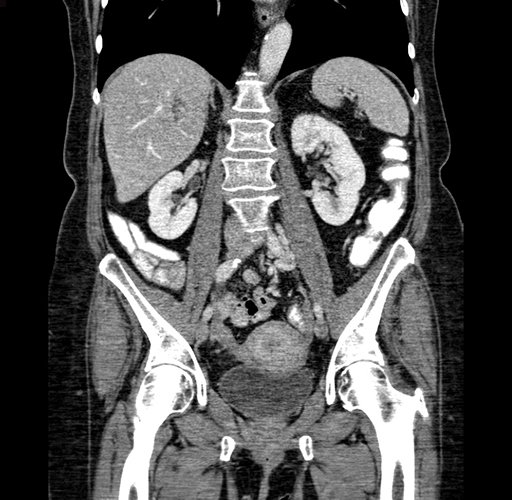

Coronal Venous